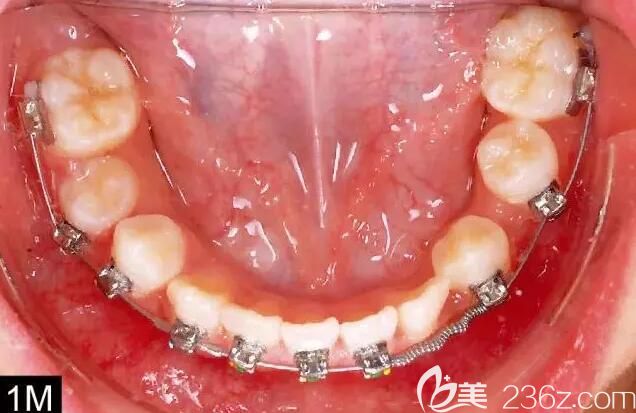

治療過程

雙牙弓選用 Damon Q? 托槽系統(tǒng) 。

在治療一個月后,下牙弓粘托槽,并放置 0.014-in 的 CuNiTi 弓絲,并在#21 和 24 牙間放置螺旋開大簧以打開空間,然后接下來的一個月,在下頜頰棚區(qū)左下磨牙 (#19) 近中根植入一顆種植釘。以種植釘為支抗的彈性橡皮鏈牽拉 #21 牙向后,為阻生牙打開空間。